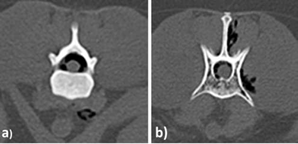

Se realizó un estudio de tomografía helicoidal multicorte (TEM) de columna Tora-co-lumbar realizado en posición supina, con adquisición volumétrica de 1,0 mm y cortes de 5 mm desde T8 a S1. En la TEM se identificó alineación longitudinal y curvatura de columna toraco lumbosacra anteroposterior de aspecto conservado, sin observarse signos en relación a listesis ni fracturas. Se evidenció aire intrarraquídeo compatible con Neumorraquis y enfisema de partes blandas pre y paravertebrales toraco lumbares, Dicho producía cambios compresivos sobre el cordón medular (Figuras 2-4). Sobre la base de los hallazgos por TEM y el mal pronóstico debido al severo daño neurológico, los responsables del paciente tomaron la decisión de realizar la eutanasia.

El NR puede ser clasificado como interno (intradural) y externo (extradural). El NR externo generalmente no produce alteraciones, sin embargo, el NR interno suele relacionarse con procesos traumáticos encefálicos y es un indicador de lesión grave11. La localización y distribución del aire dentro del canal espinal dependerá del sitio de disección del aire, del volumen de aire intraespinal, de la capacidad del espacio intraespinal y el posicionamiento del paciente. En la NR externa, el aire epidural generalmente se ubica en la región epidural dorsal, ya que es menos resistente debido a la menor cantidad de tejido conectivo, esto al compararlo con la red vascular ventral12. La TEM, es la herramienta de elección para el diagnóstico de esta lesión1. Sin embargo, la diferenciación entre un NR intra y extradural puede ser complicado, por lo que es indispensable realizar el monitoreo del estado neurológico del paciente.